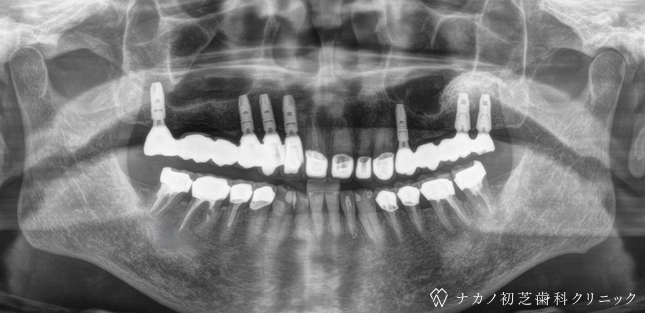

インプラント・7本 (60代男性)

-

BEFORE

AFTER

年齢 60代男性

治療内容 インプラント治療7本(骨造成の併用)

インプラント治療とは、歯を抜いた所にチタン製の人工歯根を埋入し、その上に歯を入れる方法です。骨を増やすことで、より審美的に治療が出来ました。費用 1本 400,000円(税込 440,000円)

リスク・副作用

腫れ・疼痛・違和感を感じるなどの症状を生じることがあります。